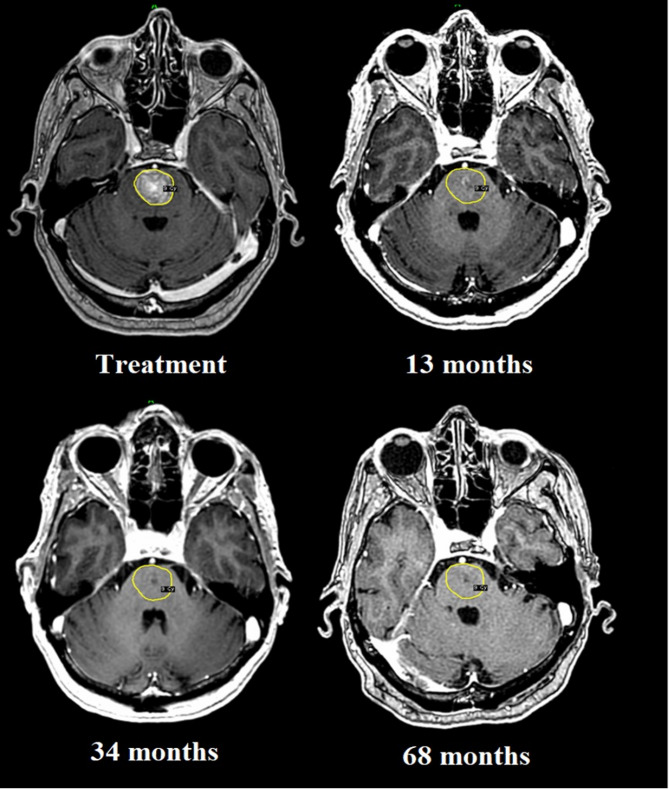

Methods: 29 patients with 35 brain metastases deemed not to be candidates for surgery, radiotherapy or systemic treatment were treated with MRI-guided adaptive Gamma Knife radiosurgery in 3 separate sessions with a 72-hour interval. Customised synchronous double-dose prescriptions were systematically utilised at each session. Estimated survival at pre-treatment was fewer than 4 weeks due to the targeted intracranial lesions. A retrospective analysis was conducted on the whole cohort, with particular emphasis on those surviving 12 months and beyond.

Results: The median overall survival was 7.3 months, with a follow-up of 7.5 years. Survival at 6, 12, 24, 36, 48 and 60 months was 62%, 41%, 17%, 14%, 10% and 7%, respectively. Local tumour control (LTC) at 1 year was 75%. 4 patients developed local recurrence late on follow-up, with a survival ranging between 12 and 40 months. 2 patients were alive at the time of submission (115- and 117-months post-treatment) with no sequelae; the remainder succumbed to general disease progression, with neurologic death being avoided throughout the whole cohort. Adverse radiation effects (ARE) were reported in 5 patients, of which 4 remained asymptomatic throughout follow-up.